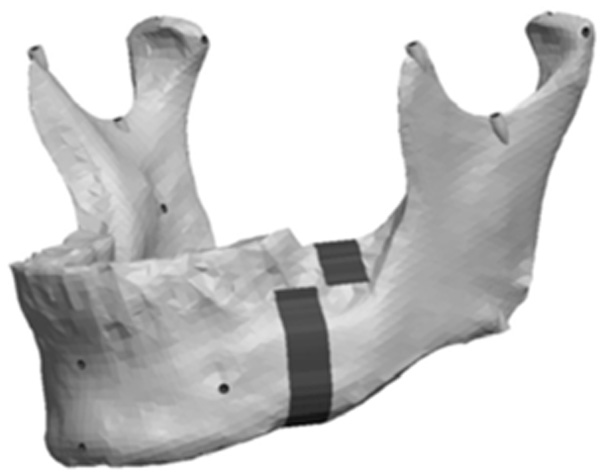

The Body section was located 43mm anterior to Cs as a plane perpendicular to the occlusal plane. The cut extended 8mm into the body before extending 10mm anterior at a 90° angle. The cut then continued vertically at 90° through the remaining body of the mandible forming a “Z-pattern” type cut. Fig. (11) outlines the location and pattern of the section made to the body of the mandible to create the body asymmetry. From this section an anteroposterior asymmetry of up to 9mm were constructed in the body region with 3mm increments. Fig. (12) represents a model with anteroposterior body asymmetry.